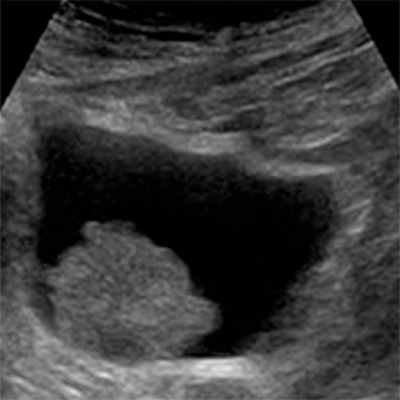

- Ультразвуковая диагностика (УЗИ). Дает возможность увидеть большие образования, и выявить изменения в почках.

УЗИ мочевого пузыря и почек, при котором можно визуализировать саму опухоль и состояние верхних мочевых путей.

- Трансабдоминальное (поверхностное) УЗИ. Данное диагностирование способно обнаружить неоплазию размером свыше 5 мм, находящуюся в большинстве случаев на боковых пузырных стенках. Эффективность исследования: неоплазия до 5 мм - 37%; опухоль диаметром свыше 5 мм - 83%.

- Для диагностирования опухолей в шейке органа делают трансректальное или трансвагинальное сканирование. В ряде случаев проводится эндолюминальная эхография. Это исследование при помощи ультразвукового прибора, введённого в мочевой пузырь через естественное отверстие. Точность определения патологии - 94%.

Большое значение в диагностике опухолей мочевого пузыря имеют лучевые методы: УЗИ, КТ, МРТ. Они позволяют неинвазивно выявить новообразование при профилактическом осмотре (УЗИ), на предоперационном этапе определить степень распространенности опухолевого процесса (МРТ, КТ), а также отследить результаты лечения (МРТ, КТ).